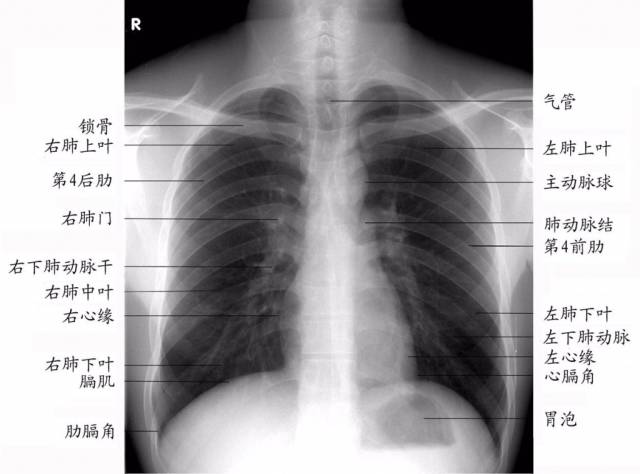

胸片上的肺纹理

在正位胸片上,肺纹理自肺门向肺野中、外带延伸,且逐级变细,至肺野外围几乎不能辨认。在正常时,下肺野肺纹理比上肺野多而粗,而右下肺野肺纹理比左下肺野多而粗。

正常胸片